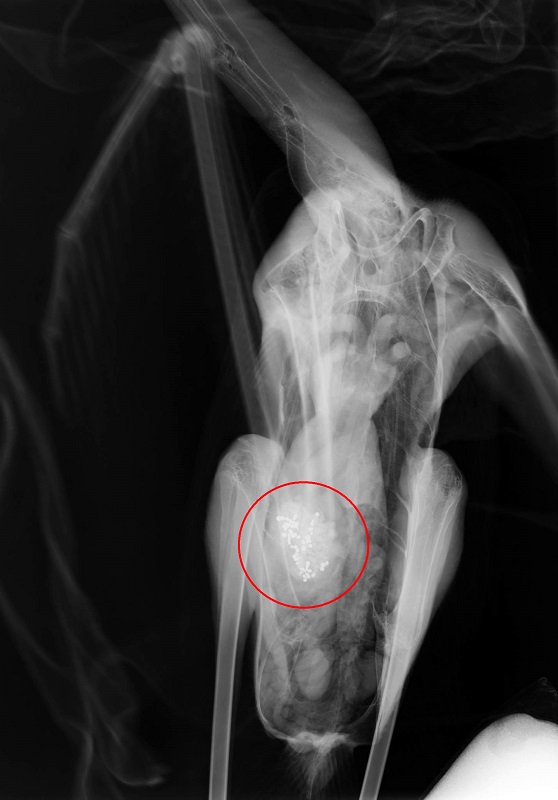

«Τα περισσότερα πουλιά έχουν εντοπιστεί στον Άγιο Μάμα και λίγα άτομα στην Επανομή, το Αγγελοχώρι και στη διαδρομή μεταξύ αυτών των υγροτόπων, καθώς τα πουλιά μετακινούνται μεταξύ αυτών των περιοχών για να τραφούν. Όλα τα φοινικόπτερα που φτάσανε στις εγκαταστάσεις μας για περίθαλψη είναι με συμπτώματα μολυβδίασης, ενώ τόσο οι νεκροψίες που έχουμε διεξάγει, όσο και οι ακτινογραφίες, δείχνουν ότι έχουν καταπιεί σκάγια», αναφέρει η Πηνελόπη Καραγιάννη, ορνιθολόγος της εθελοντικής οργάνωσης Δράση για την Άγρια Ζωή.